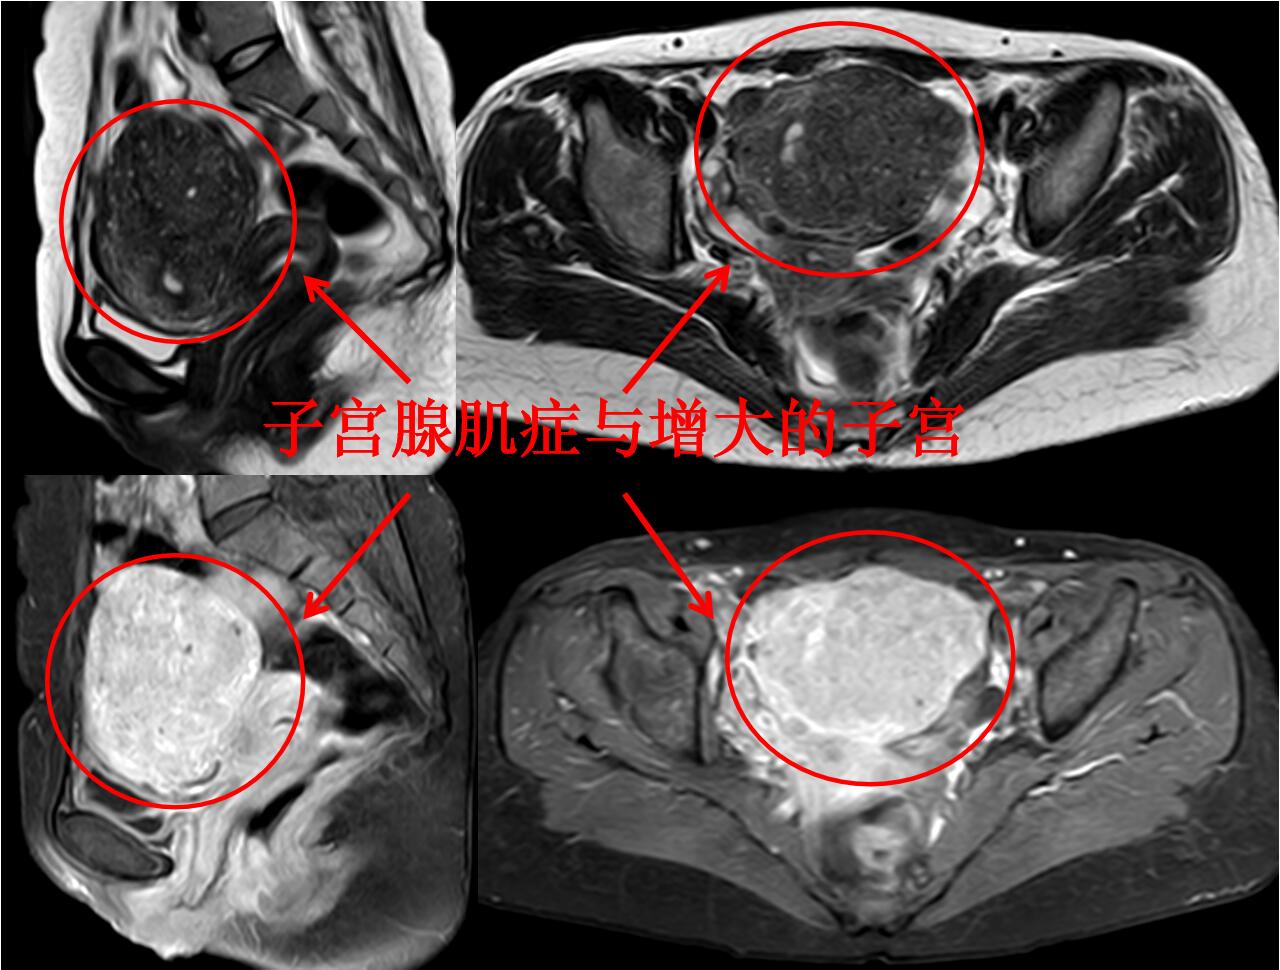

门诊磁共振检查:子宫明显增大(10.8*9.2*8.7cm3),子宫腺肌症,以宫底及后壁明显(如下图)。

介入微创消融治疗后无明显痛经,3个月后复查磁共振显示:子宫腺肌病病灶灭亡,子宫缩小(如下图)。